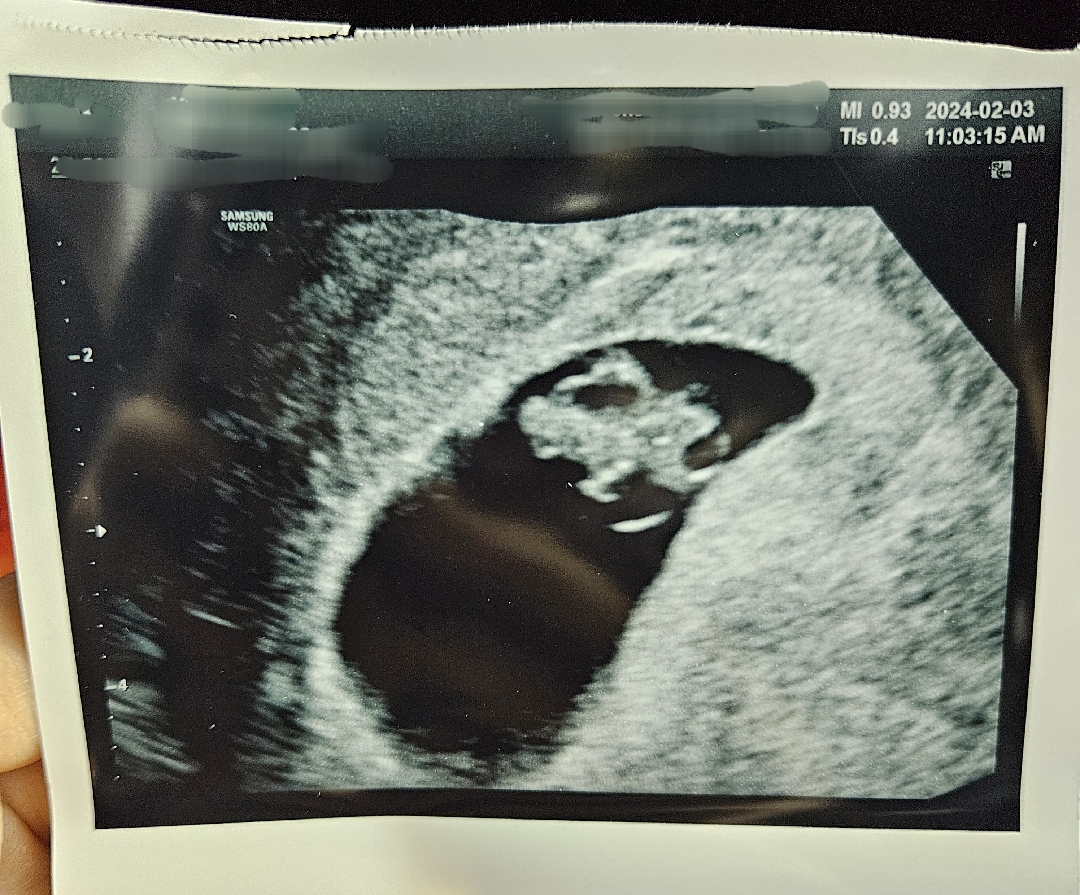

2주 전인 5주 때엔 아기집만 보구 6주 들어서면서 입덧이 체덧으로 와서 힘듦을 느끼구 있었는데 어젠 또 너무 식욕이 좋아서 이것 저것 잘 먹었더니 또 갑자기 애기 걱정이 돼서 병원 가서도 긴장이 돼 혼났어요..ㅜ 초음파로 여기저기 보다보니 2주 전과는 다르게 훌쩍 커버린 아가 보고는 눈물이 또르르....🥲 맘이 정말 놓이더라구요. 심장박동은 159로 아주 건강히 잘 있다고 하네요ㅎㅎ 집에 와서 심장박동소리 다시 듣는데 왜 눈물이 나는진 모르겠지만 혼자서 또 폭풍오열을 했네요ㅠ_ㅠ 오늘은 이렇게 마음 놓지만 2주 동안 또 검진 날짜 다가오면서 걱정이 쌓여갈 듯요ㅋㅋㅋ 그래도 여기 들어와서 한번씩 걱정 덜고 가네요ㅎㅎ 모든 아가들 다 건강히 쑥쑥 자라길 빕니다♡

오늘로 7주 4일차였어요ㅎㅎ